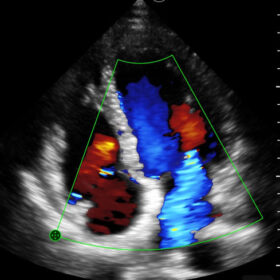

Mindray I3P WiFi Probe Image Gallery and Videos

Display mode: B, B/M, and Color, PW, PDI